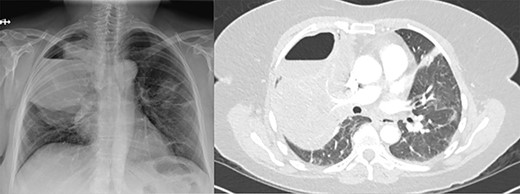

As the patient lived several hours away from the closest hospital, we obtained a second post-operative chest CT to ensure that she had no additional collections and to establish a new baseline. This demonstrated a 4 cm collection in the subcutaneous space. We aspirated the fluid, which showed no growth. The patient was discharged on a course of oral moxifloxacin. A repeat chest CT 4 weeks after Clagett closure was obtained and showed improved aeration of the right upper lobe (Fig. 4).